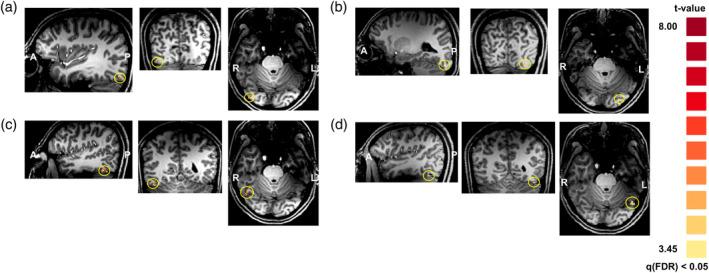

Given that the brain is a dynamic system, the temporal characteristics of brain function are important. Previous functional magnetic resonance imaging (fMRI) studies have attempted to overcome the limitations of temporal resolution to investigate dynamic states of brain activity. However, finding an fMRI method with sufficient temporal resolution to keep up with the progress of neuronal signals in the brain is challenging. This study aimed to detect between-hemisphere signal progression, occurring on a timescale of tens of milliseconds, in the ventral brain regions involved in face processing. To this end, we devised an inter-stimulus interval (ISI) stimulation scheme and used a 7T MRI system to obtain fMRI signals with a high signal-to-noise ratio. We conducted two experiments: one to measure signal suppression depending on the ISI and another to measure the relationship between the amount of suppression and the ISI. These two experiments enabled us to measure the signal transfer time from a brain region in the ventral visual stream to its counterpart in the opposite hemisphere through the corpus callosum. These findings demonstrate the feasibility of using fMRI to measure ultra-fast signals (tens of milliseconds) and could facilitate the elucidation of further aspects of dynamic brain function.

鉴于大脑是一个动态系统,脑功能的时间特征很重要。先前的功能磁共振成像 (fMRI) 研究试图克服时间分辨率的限制,以研究大脑活动的动态状态。然而,找到一种具有足够时间分辨率的 fMRI 方法来跟上大脑中神经元信号的进展是具有挑战性的。本研究旨在检测参与面部处理的腹侧脑区中数十毫秒时间尺度的半球间信号进展。为此,我们设计了一种刺激间间隔 (ISI) 刺激方案,并使用 7T MRI 系统获得具有高信噪比的 fMRI 信号。我们进行了两项实验:一项是测量 ISI 依赖性的信号抑制,另一项是测量抑制量与 ISI 之间的关系。这两项实验使我们能够通过胼胝体测量腹侧视觉流中的一个脑区到对侧半球的对应脑区的信号传递时间。这些发现表明使用 fMRI 测量超快信号(数十毫秒)是可行的,并且可以促进对动态脑功能的进一步方面的阐明。